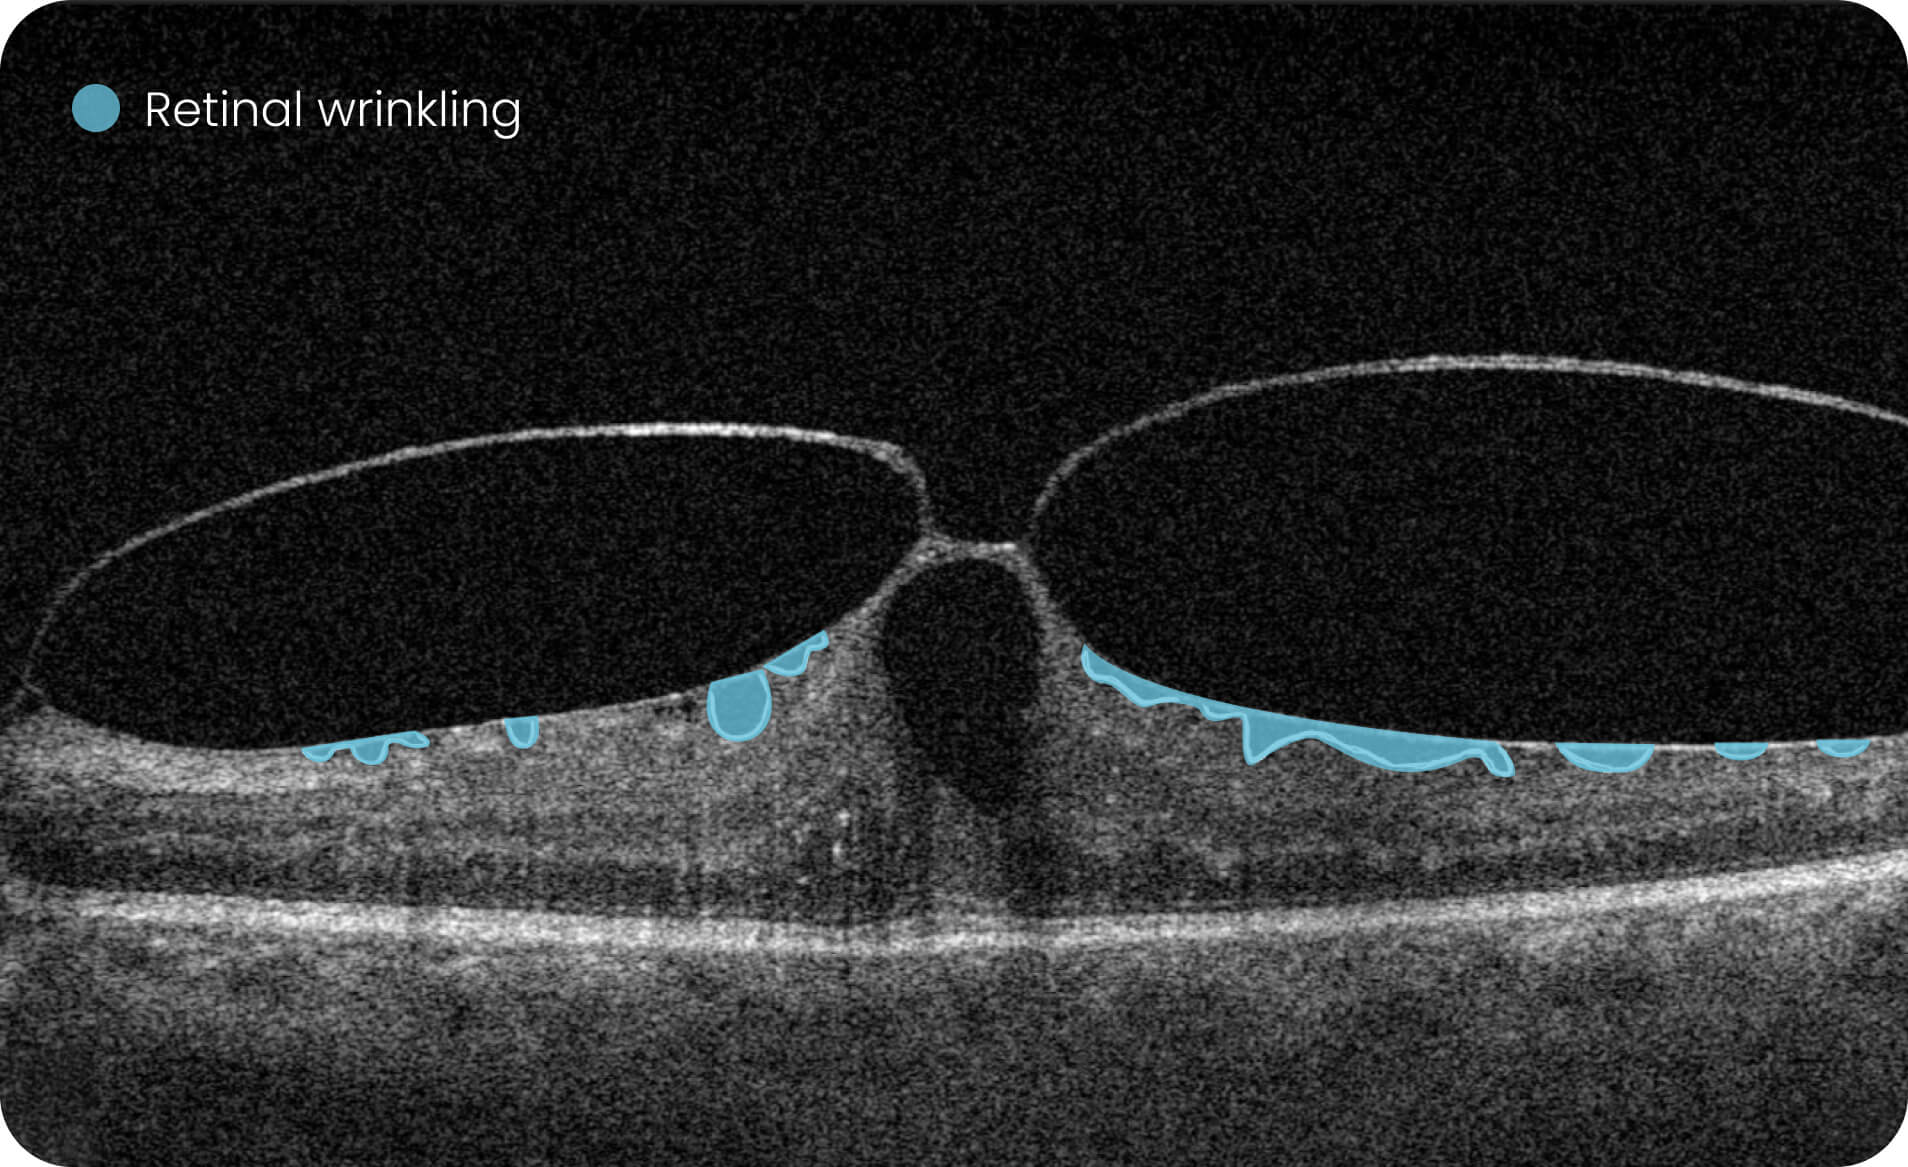

Characterization and visualization of OCT features commonly studied in Geographic Atrophy (GA), including hypertransmission, RPE atrophy, neurosensory retinal atrophy, and EZ changes.

The GA Progression feature provides tools for research-oriented visualization and comparison of OCT imaging data across multiple visits. Users can review changes in areas associated with geographic atrophy (GA) and related imaging features through percentage-based displays, maps, and graphs.

Quantitative, image-derived measurements of GA-related features and associated biomarkers for research analyses.

Visualization of spatial relationships, including the estimated distance between GA-associated regions and the foveal area, as well as macular involvement.

Altris is a web platform developed by professionals with expertise in retinal imaging. We’ve collected a large number of OCT scans, and our team has manually annotated thousands of them to develop the Altris system, an artificial intelligence geographic atrophy research USA platform, which can: